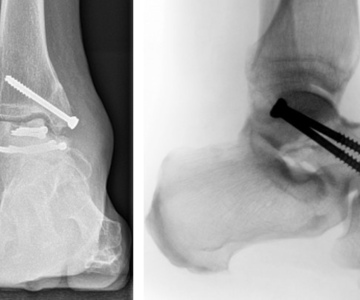

Консервативне та оперативне лікування

Консервативне та оперативне лікування захворювань і травматичних пошкоджень опорно-рухового апарату будь-якої складності. Сучасні методи діагностики, лікування та остеосинтезу - інтрамедулярні блокуючі стержні, пластини з мінімальним контактом, малоінвазивні методи остеосинтезу, ендопротезування суглобів, артроскопія, реконструктивна хірургія, лікування хибних суглобів...

травматологія-ортопедія

З нами співпрацюють травматологи-ортопеди з багаторічним досвідом роботи. Фахівці з лікування травм і захворювань опорно-рухового апарату - консервативне і оперативне лікування захворювань суглобів у дітей і дорослих, ендопротезування суглобів, сучасні методи остеосинтезу, артроскопія, реконструктивна хірургія ...